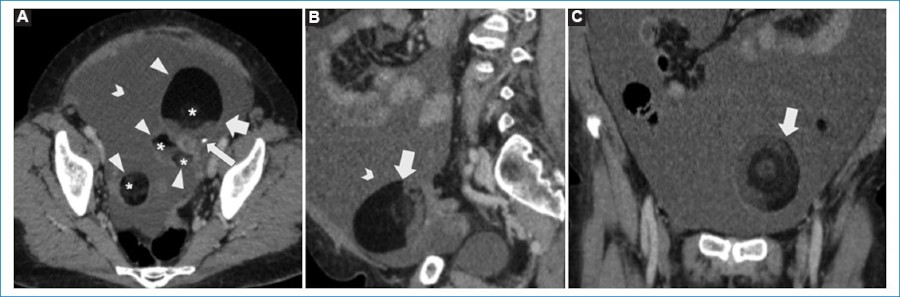

La TCMD es una técnica de alta sensibilidad diagnóstica de esta forma de presentación, mostrando un quiste con interfaz líquido-grasa con una imagen central con densidad de partes blandas en relación con el nódulo de Rokitansky o tapón dermoide, y en algunos casos con calcificaciones intratumorales (Fig. 1). A su vez, la grasa contenida en estas lesiones puede ser visualizada en RM con aumento de señal en secuencias ponderadas en T1 y con caída de la señal en las secuencias con saturación grasa. Algunas veces pueden resultar de ayuda las secuencias GRE debido al bajo contenido lipídico intracelular4.

En 1991, es Muramatsu quien por primera vez realiza una analogía de esta forma de presentación, denominándola “signo de la bola flotante”. Posterior al estreno de la serie Pokémon, esta presentación también comienza a ser conocida como el “signo de la Pokebola”1,3 (Fig. 2).